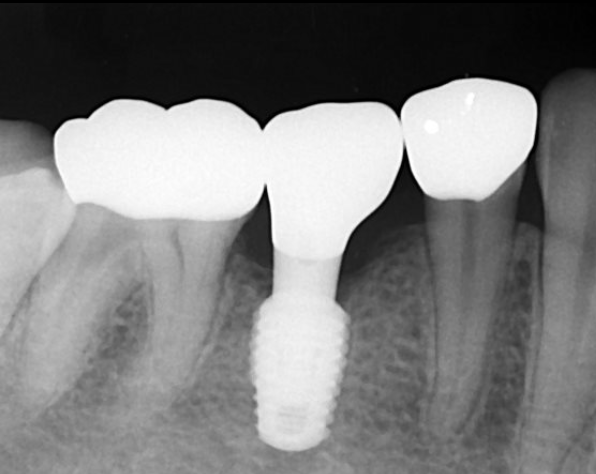

SET後のデンタルX線写真